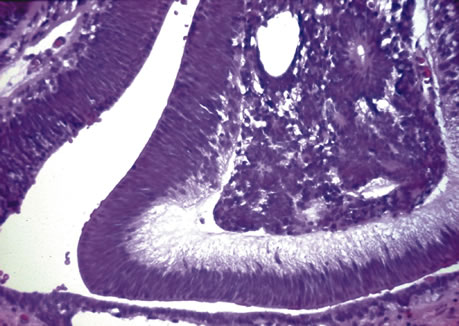

Iris cysts can be classified based on their location.26 In general, iris cysts are of the pigment epithelium or of the iris stroma. Most iris epithelial cysts remain stable and do not progress. If the cyst is located in an area of iris pigment epithelium, the cyst will fail to transilluminate. In contrast, if the iris cyst is more peripheral and located near the ciliary body nonpigmented epithelium, the cyst may allow transillumination. As its name implies, a cyst of the pigment epithelium is lined by the iris pigment epithelial cells. On the other hand, cysts of the iris stroma are lined by stratified squamous epithelium with goblet cells and may resemble conjunctival epithelium (Fig. 1). These findings and the fact that stromal cysts are usually found in infants support the idea of a congenital rest of ectopic surface epithelium as the source of these lesions.

Fig. 1. Iris cyst. Iris stromal cyst lined by stratified epithelium that resembles conjunctival epithelium. (Hematoxylin-eosin ×25.)